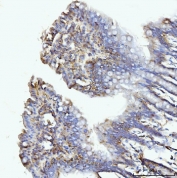

Immunohistochemistry of GLUL Antibody Rabbit Polyclonal in human gastric adenocarcinoma tissue. Formalin-fixed, paraffin-embedded human gastric adenocarcinoma sections demonstrate cytoplasmic HRP-DAB brown staining in malignant gland-forming epithelial cells consistent with Glutamate-ammonia ligase (Glutamine synthetase) expression. Tumor epithelial cells show moderate to strong cytoplasmic staining, while surrounding stromal cells display comparatively weaker signal. Heat-induced epitope retrieval was performed by boiling tissue sections in pH 8 EDTA for 20 min followed by cooling prior to antibody incubation.